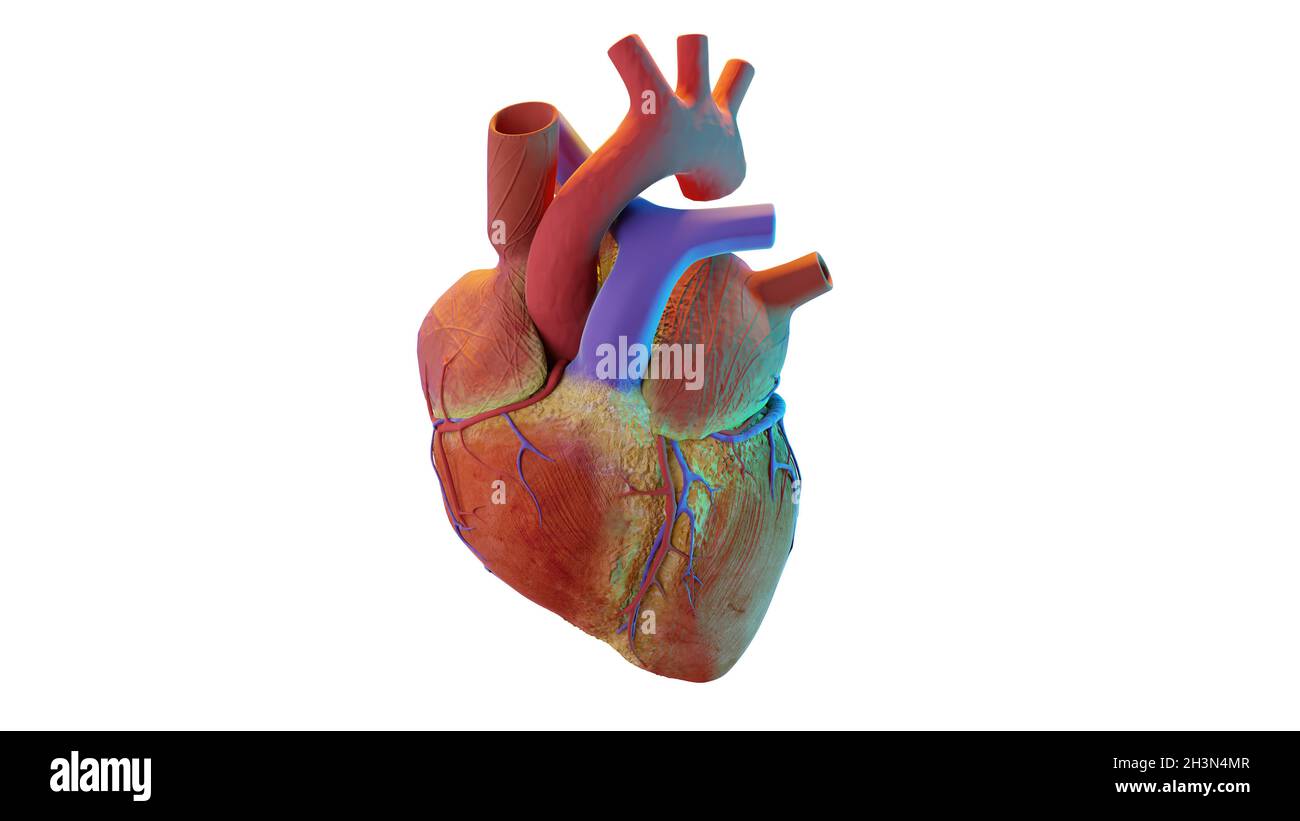

human heart. realistic image isolated, Correct anatomical heart with venous system, 3d render Stock Photohttps://www.alamy.com/image-license-details/?v=1https://www.alamy.com/human-heart-realistic-image-isolated-correct-anatomical-heart-with-venous-system-3d-render-image449778247.html

human heart. realistic image isolated, Correct anatomical heart with venous system, 3d render Stock Photohttps://www.alamy.com/image-license-details/?v=1https://www.alamy.com/human-heart-realistic-image-isolated-correct-anatomical-heart-with-venous-system-3d-render-image449778247.htmlRM2H3N4MR–human heart. realistic image isolated, Correct anatomical heart with venous system, 3d render